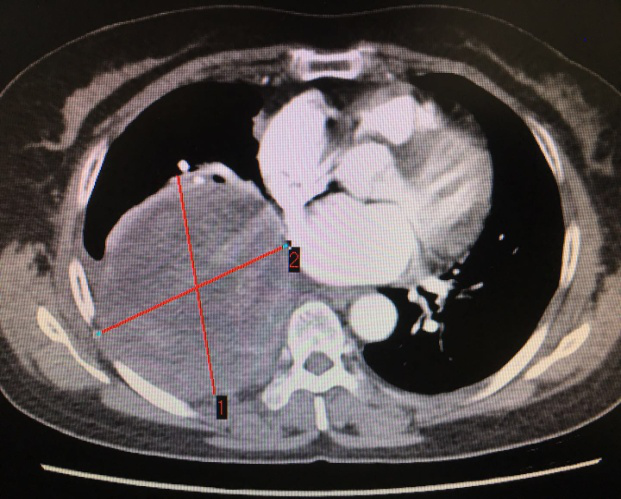

患者CT影像 (标记处为肿瘤)

李旭主任仔细为患者查体,经过严密的病情分析后,考虑肿瘤巨大,侵犯心包和下肺组织,决定先行肺穿刺,排除其他恶性肿瘤。最终穿刺病理显示,陈阿姨患的是神经鞘瘤,这让李主任松了一口气:“还有手术的机会!”。